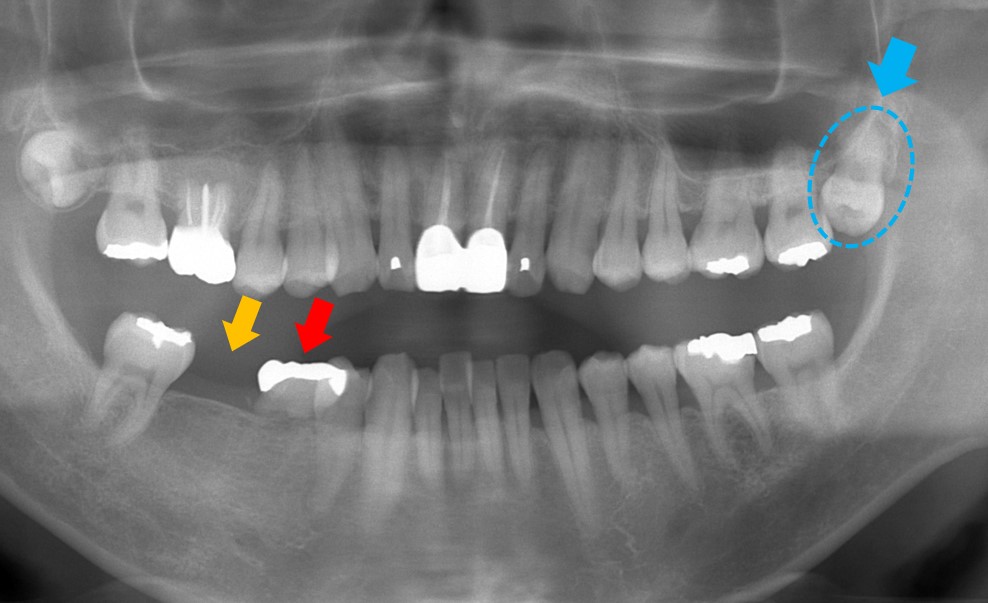

オレンジ矢印の部分が欠損しています。赤矢印は乳歯ですが、動揺もせず何十年もこのままの状態であることから、乳歯はそのまま処置せずに欠損している部分(オレンジ矢印部分)に青矢印の親知らずを移植する計画としました。